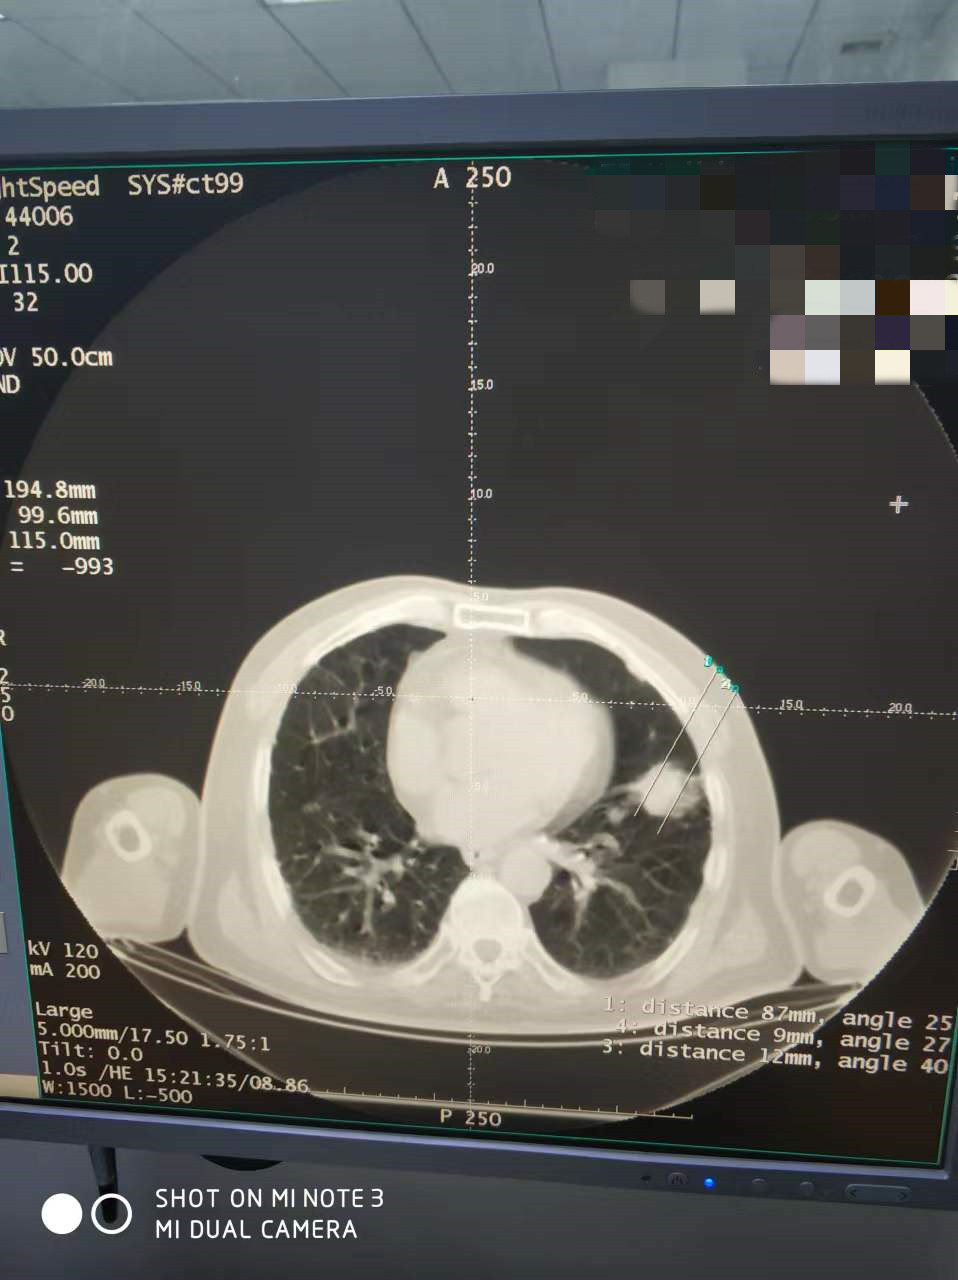

上一篇:2022年4月份肺部氩氦刀手术